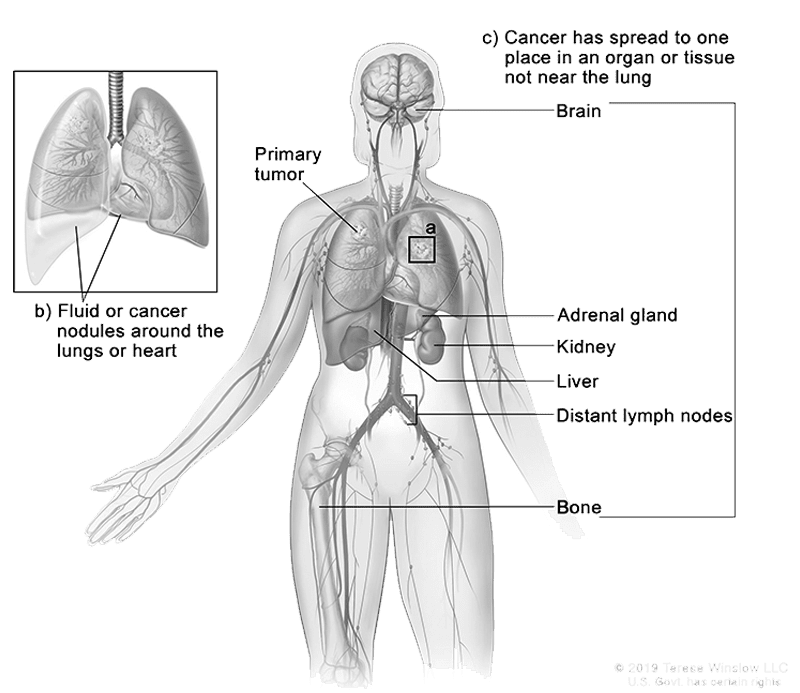

- Where did my cancer start and where has it spread to?

Image shows common location for this cancer type. Please ask your Dr. about your diagnosis.